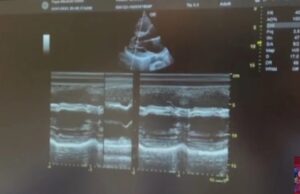

Кај 29-годишен Албанец срцето и другите органи се на спротивната страна

реклама        Во болница во Лондон, кај 29-годишен Албанец, кој се пожалил на здравствени проблеми,...